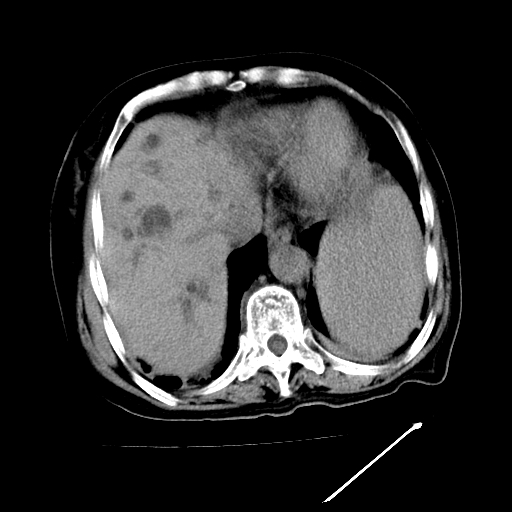

以下是引用随光逐影在2009-4-7 8:21:00的发言:[br]肝内外胆管多发性结石并肝内外胆管扩张;胆系感染。